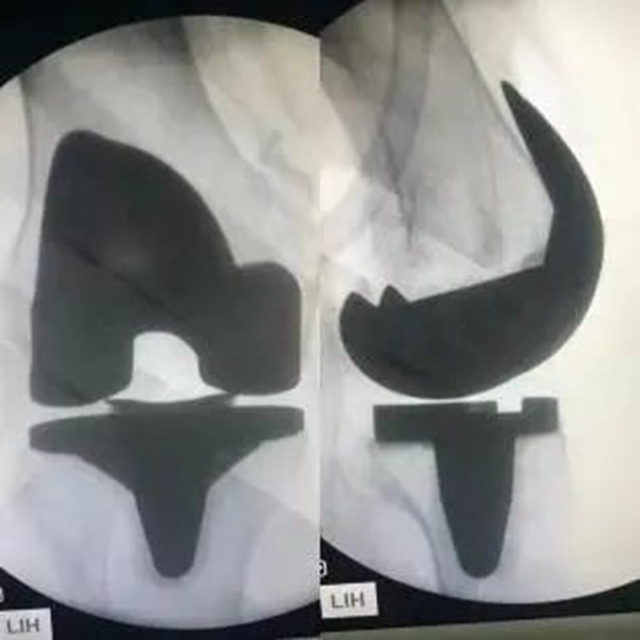

术后X片

“我母亲7年前做右膝关节置换手术时,人工关节花费了接近4万元,而这次手术中张教授使用的假体才4000多元,为我们家节省了3万多呢!”郭婆婆的女儿毛女士说到。